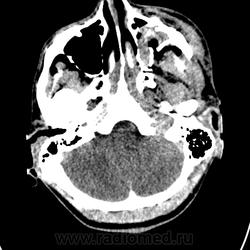

Доброе утро, уважаемые коллеги! Ночью привезли молодого человека с ДТП. Находится  в коме, множественные переломы лицевого скелета. Помогите описать их. Спасибо.

Ну, кости, конечно лучше смотреть в костном фильтре, а не в костном окне мягкотканных изображений. Поэтому чем могу: оскольчатые переломы передней и задней стенок левой верхнечелюстной пазухи со смещением, перелом верхней стенки левой в/ч пазухи (нижней стенки левой орбиты), (тут обязательно посмотреть МПР на предмет пролапса мягких тканей орбиты в полость пазухи, но по эти дайкомам почему-то не строит); перелом левой скуловой кости, перелом левой скуловой дуги, перелом левого клиновидно-скулового шва,  перелом левого большого крыла основной кости (перелом наружной стенки левой орбиты); перелом тела основной кости (стенок клиновидных пазух); содержимое повышенной плотности (кровь) в клиновидных, левой верхнечелюстной пазухах, решетчатых клетках, левосторонний экзофтальм. Содержимое в правом наружном слуховом проходе, ячейках правого сосцевидного отростка, пристеночно в правой барабанной полости (может тоже есть перелом, но это надо вдумчиво смотреть в костно фильтре и на МПР); кравой перелом правого мыщелка затылочной кости, (возможен перелом затылочной кости справа, но это надо детально отстраивать на более тонких (0,63мм) срезах)

Интракраниально: срединные стрктуры не смещены, цистерны основания мозга не деформированы, желудочки симметричны, латеральные щели и конвекситальные борозды проослеживаются с обеих стророн. Есть снижение плотности белого вещества левой лобной доли (ушиб I вида (по Корниенко).

Кроме переломов по Ле Фор, существует перелом скулоорбитального комплекса, когда ломаются кости в области швов, соединяющих скуловую кость с верхней челюстью (передняя и заднелатеральная стенки верхнечелюстной пазухи, нижняя стенка орбиты), с основной костью (латеральная стенка орбиты) и с височной костью (скуловая дуга). При этом скуловая кость, как правило, вдавлена.

В нашем случае имеется перелом скулоорбитального комплекса слева. Кроме того, мне мерещится перелом левой латеральной стенки основной пазухи (если бы срезы были тонкие, можно было бы сказать точно). Это добавляет к перелому лицевого черепа еще и перелом основания мозгового черепа, который по определению является открытым и требует консультации нейрохирурга. Так что, смотрите тонкие срезы.

Однозначно, тут есть и перелом основания черепа (тело и большое крыло основной кости), а также небольшие эпидуральные гематомы в области кавернозного синуса и передних отделов средней черепной ямки. Так что, без нейрохирургов не обойтись...